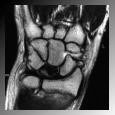

La resonancia nuclear magnética (RNM) es la prueba diagnóstica más útil porque permite el diagnóstico precoz de la enfermedad de Kienböck y evalúa los resultados tras la cirugía (figura 5). La tomografía axial computarizada (TAC) permite valorar mejor la estructura ósea y un estadiaje más preciso.

I: morfología y densidad radiológica del semilunar normal. En RNM sí se aprecia sí se aprecia de distinta condensación debido a la falta de sangre (figura 5).